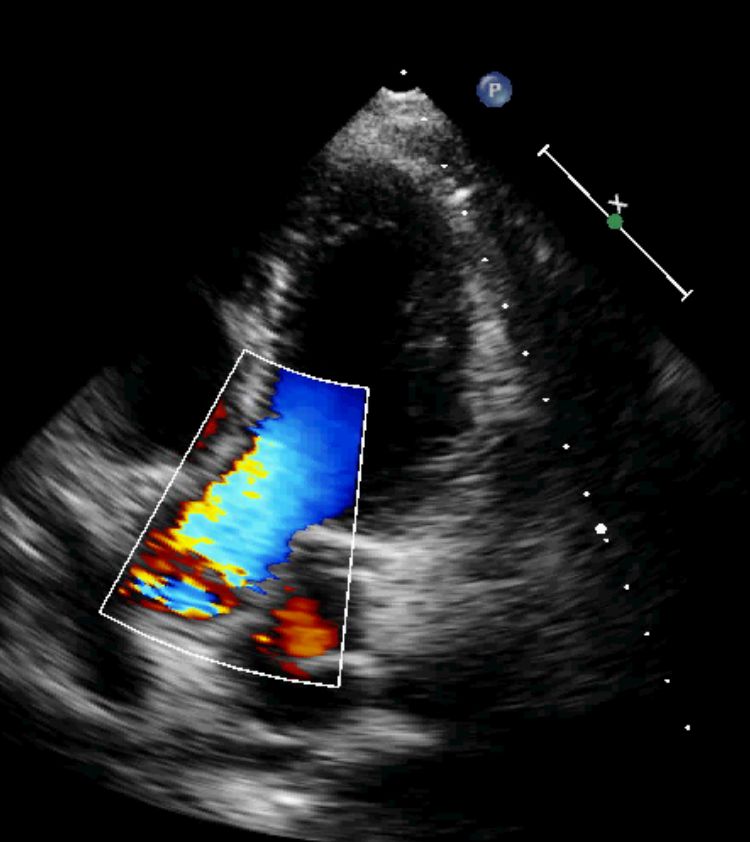

Domande su Aneurisma aortico

Buongiorno,

mio babbo in seguito ad aneurisma all'aorta ha subito un intervento dove gli hanno installato una protesi nel torace nella curva ascendente dell'aorta.

I medici hanno ipotizzato che la protesi impiantata lo scorso anno all'aorta si sia allargata o mossa e che tocchi dei nervi di bocca, gola e epiglottide e che causi questi disturbi.

chiedo io: e' possibile che una protesi artificiale all'aorta si sposti o si allarghi??? A ME SEMBRA UNA COSA ASSURDA, sto chiedendo parere anche a voi

se ho capito bene la protesi è stata impiantata 1 anno fa?! è impossibile che si sposti, fa parte integrante dell'aorta, .

E' invece possibile che vi sia un ulteriore dilatazione a monte o a valle della protesi.

Dr. Guidalberto Guidi